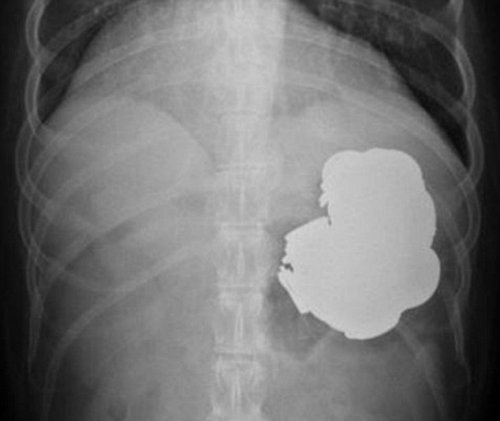

Среди проглоченного оказались: сто пятьдесят три гвоздя, сто сорок монеток, орехи, болтики и батарейка, магниты, винты и прочие железные мелочи. Врачи провели эндоскопию, введя шланг с камерой прямо ему в желудок, таким образом, они и обнаружили все это. К слову, сам пациент боли в животе с поглощением предметов не связывал. Более того, он постоянно приходил в медицинские центры, но врачи ему правильный диагноз до сих пор не ставили. Уже понадобилось более двухсот сорока эндоскопических процедур, чтобы удалить все инородные предметы.